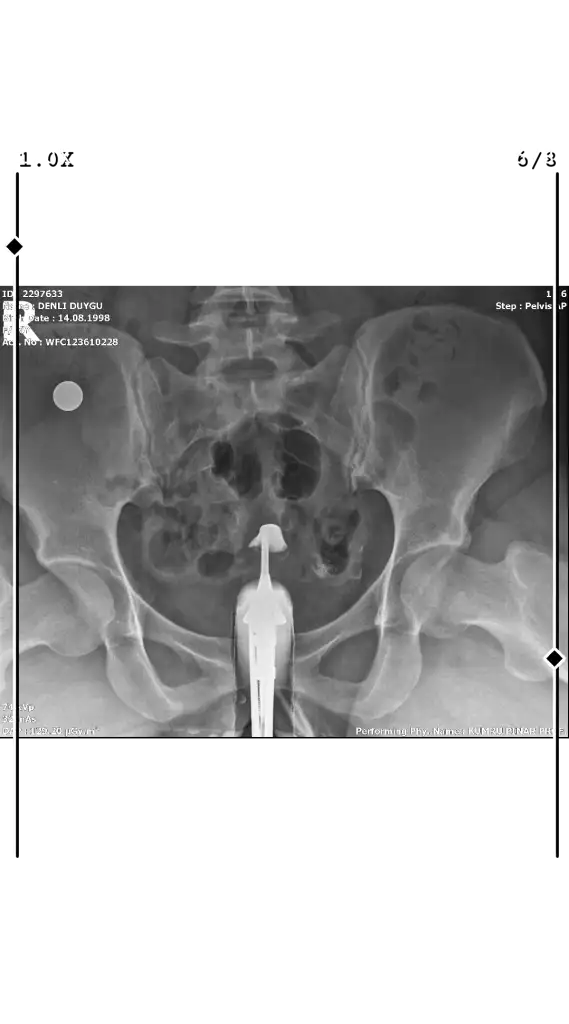

Sadece bu görüntü mü varRahim filmim bu şekilde henüz yorumlanması hiç iç açıcı görmüyorum yorumlar mısınız lütfen

Bunlar da varSadece bu görüntü mü var

Tüplerden dağılım olmamış gibi duruyor tıkalı sanırımBunlar da var

Görsellerde adınız çıkmış bilginiz olsun, rahminiz arkaya doğru mu neden o şekilde çıkmış sonuçlarda dağılım olmuş demiş ama görselde yokYorumlar mısınız lutfen

Herşey olması gerektiği gibi kameradan dolayı farklı çıkmış dediGörsellerde adınız çıkmış bilginiz olsun, rahminiz arkaya doğru mu neden o şekilde çıkmış sonuçlarda dağılım olmuş demiş ama görselde yok